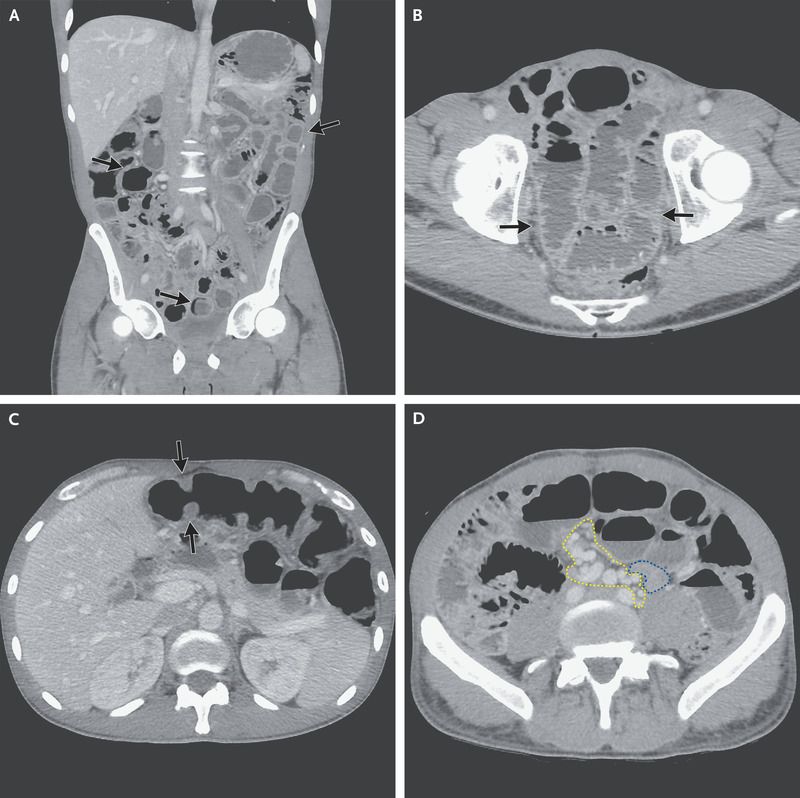

A 62-year-old man presented beside a 5-month history of abdominal distention, diarrhoea, and weight loss. The medical history was notable for the excision of a localized oral clear-cell sarcoma 2 years earlier without further treatment. The physical examination showed enlarged cervical lymph nodes and abdominal distension.

Computed tomography of the abdomen showed numerous grape-like nodules. Ultrasonographically guided biopsy of an abdominal lesion was performed, and the histopathological analysis revealed clear cell sarcoma Panel B.